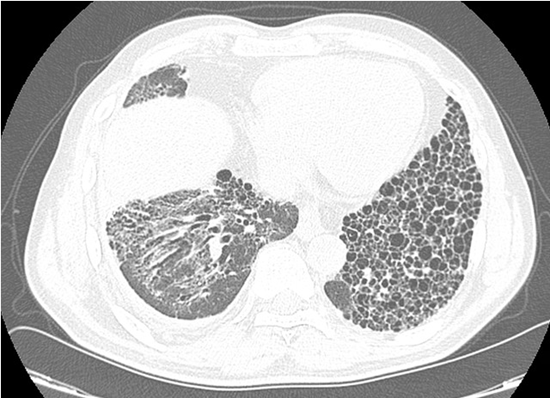

A new HRCT revealed a strikingly asymmetric fibrotic pattern a fibrotic NSIP involving the right lung, in contrast to an exuberant usual interstitial pneumonia (UIP) pattern in the left lung (Figure 1B). Given the cutaneous findings, the deteriorating clinical course and the uncommon radiologic findings, extended serologic testing, including a myositis panel, was repeated, demonstrating a positivity for anti–MDA5 antibodies.

Figure 1B: HRCT scan (2025): A striking atypical asymmetric pattern of a fibrotic NSIP at the right lung base and an exuberant UIP pattern at the left lung.

Anti-MDA5 myositis is associated with dermatomyositis and progressive interstitial lung disease, characterized by high early mortality, poor response to immunosuppression, and minimal (amyopathic) muscle involvement [1]. Radiologically, organizing pneumonia and NSIP predominate, whereas UIP is uncommon [2], rendering the unilateral UIP pattern in this case particularly notable. Antifibrotic therapy (nintedanib) was added to ongoing MMF treatment.